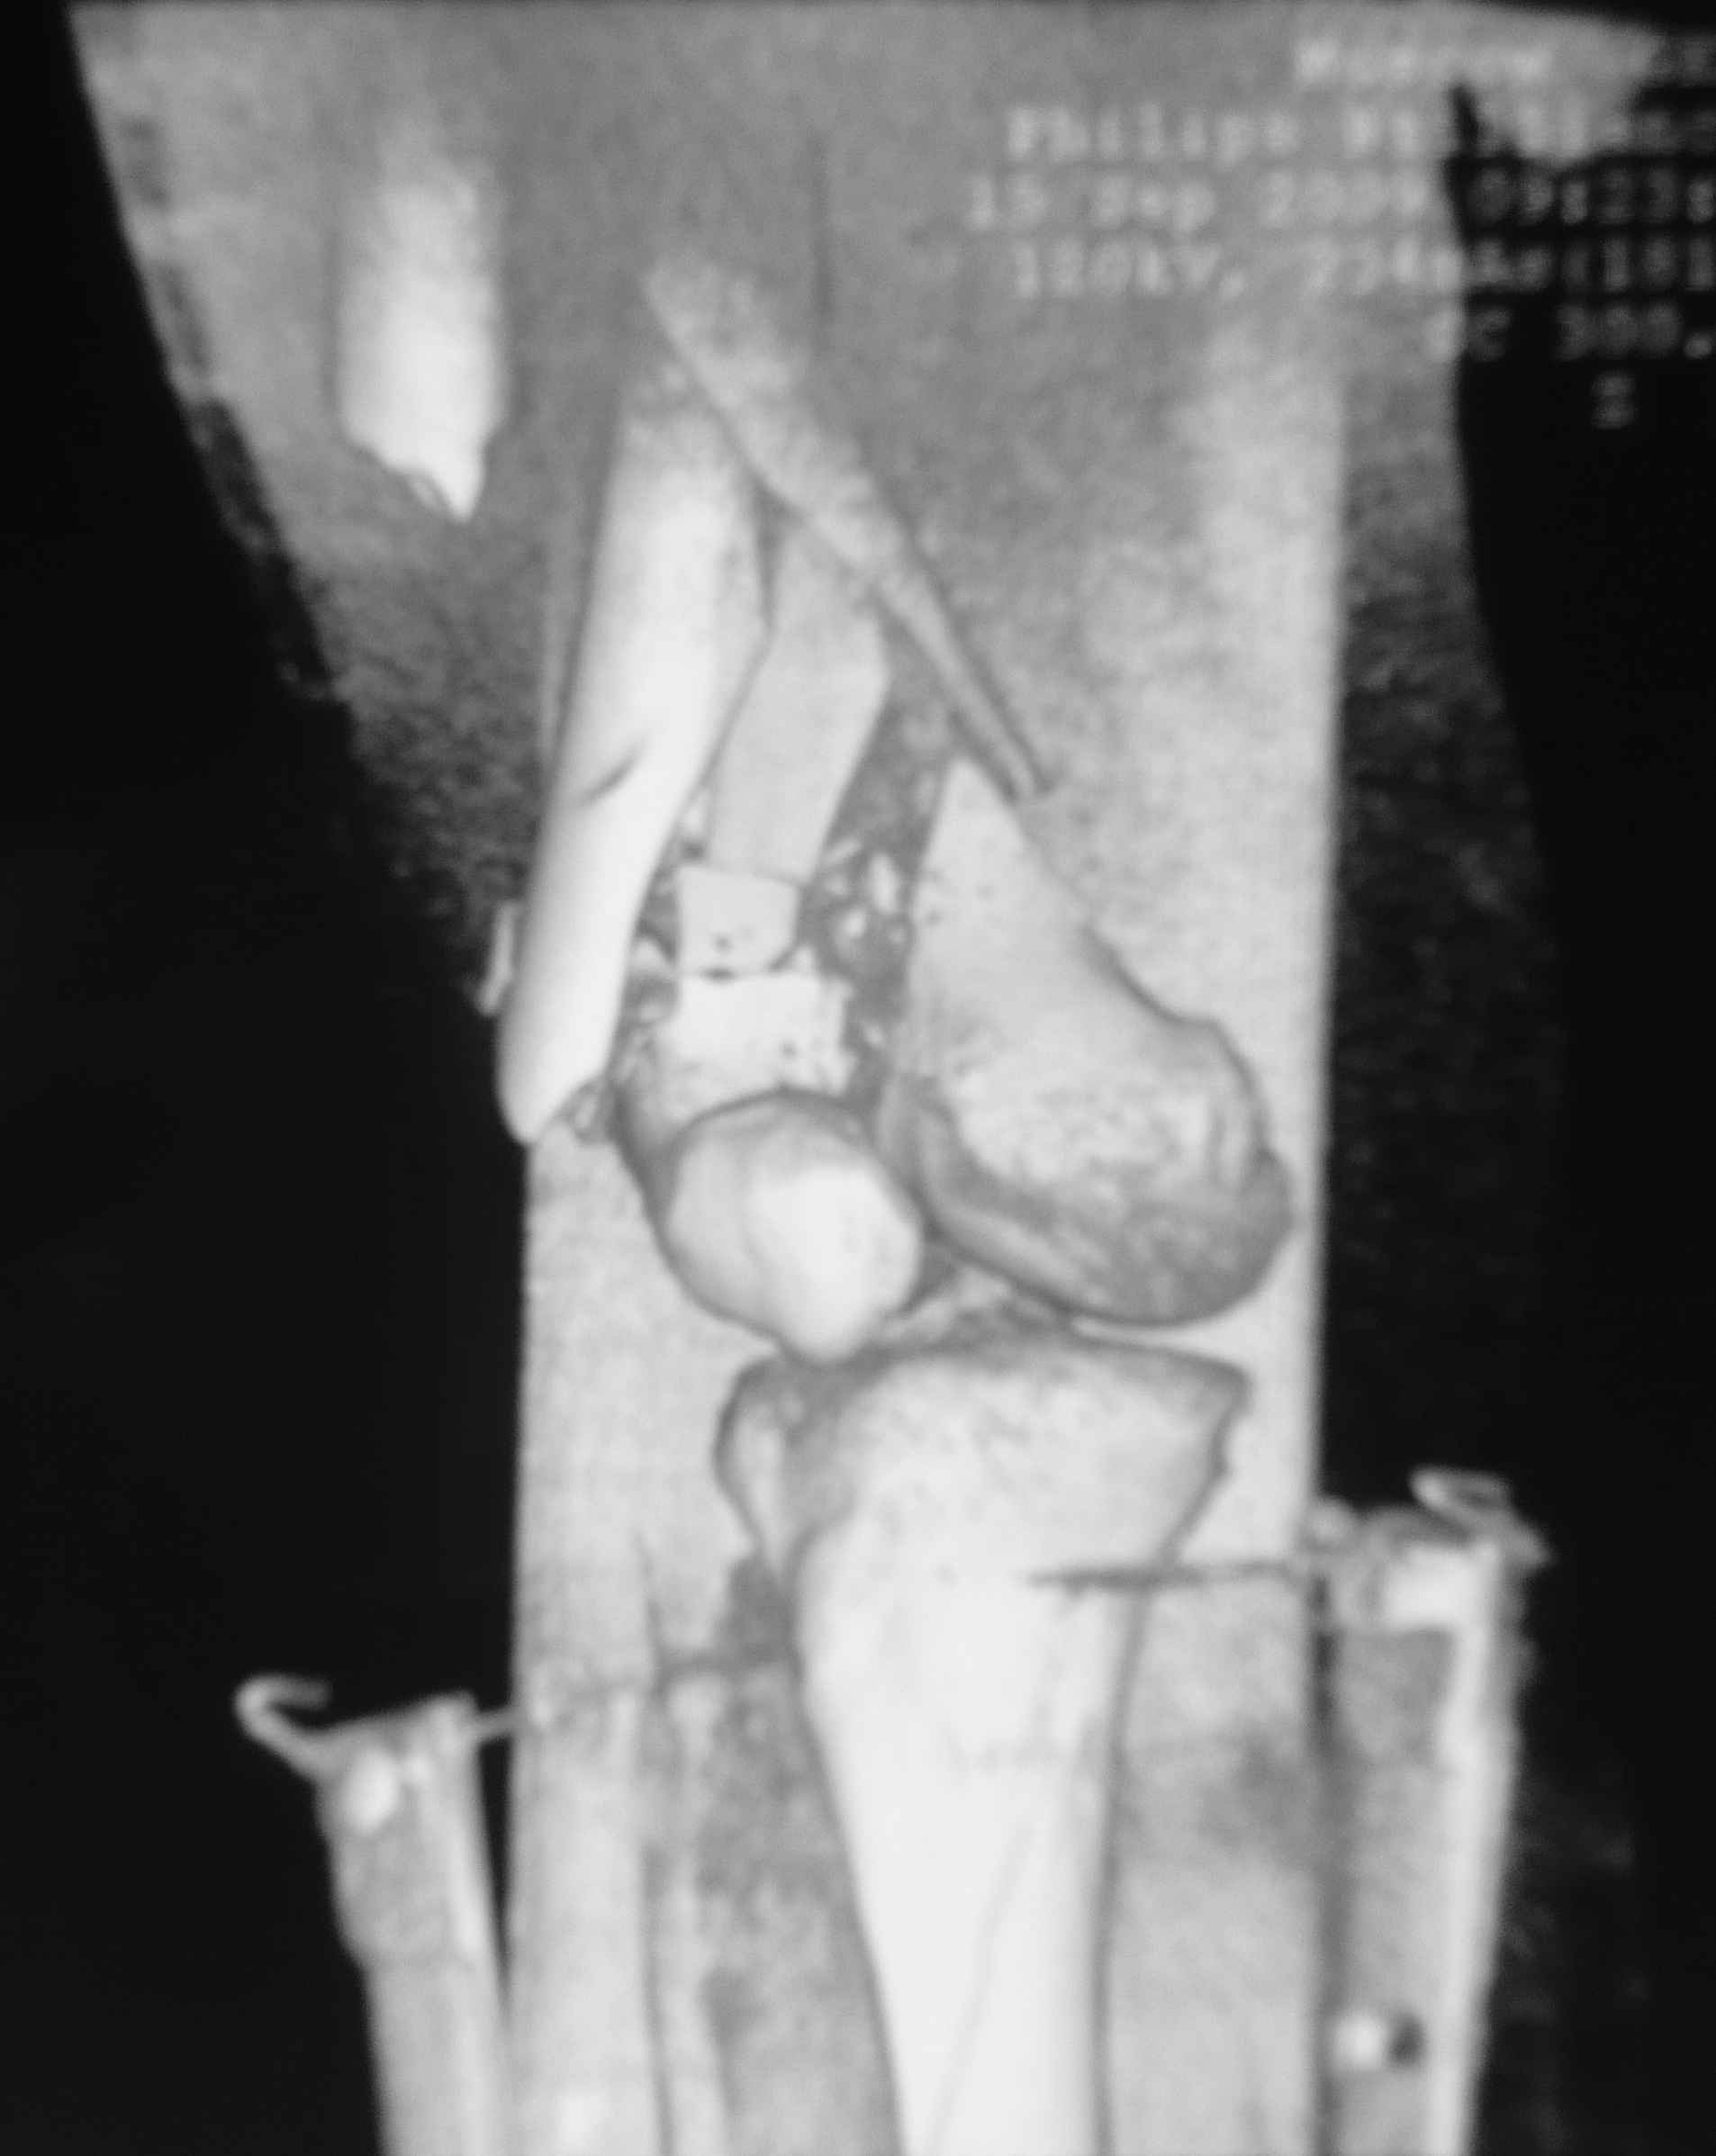

Это перелом не нижней трети, а дистального суставного конца, с распространением на диафиз. Что-то между C2 и C3. Но пока ближе к C2 по увиденному - вторую проекцию еще не показали.

На профиле стало видно, что открываться придется, это перелом C3, хотя можно назвать и C2+, т.е. с еще и фронтальным раскалыванием одного мыщелка. Надо сделать медиальную артротомию, ступеньку на внутреннем мыщелке устранить, ввести либо несколько временных спиц спереди назад, или сразу винт вдоль эллипса мыщелка. А дальше как выше написано - дистрактор, и штифтовать. Учитывая наличие открытого колена - вполне уместно ретроградно.